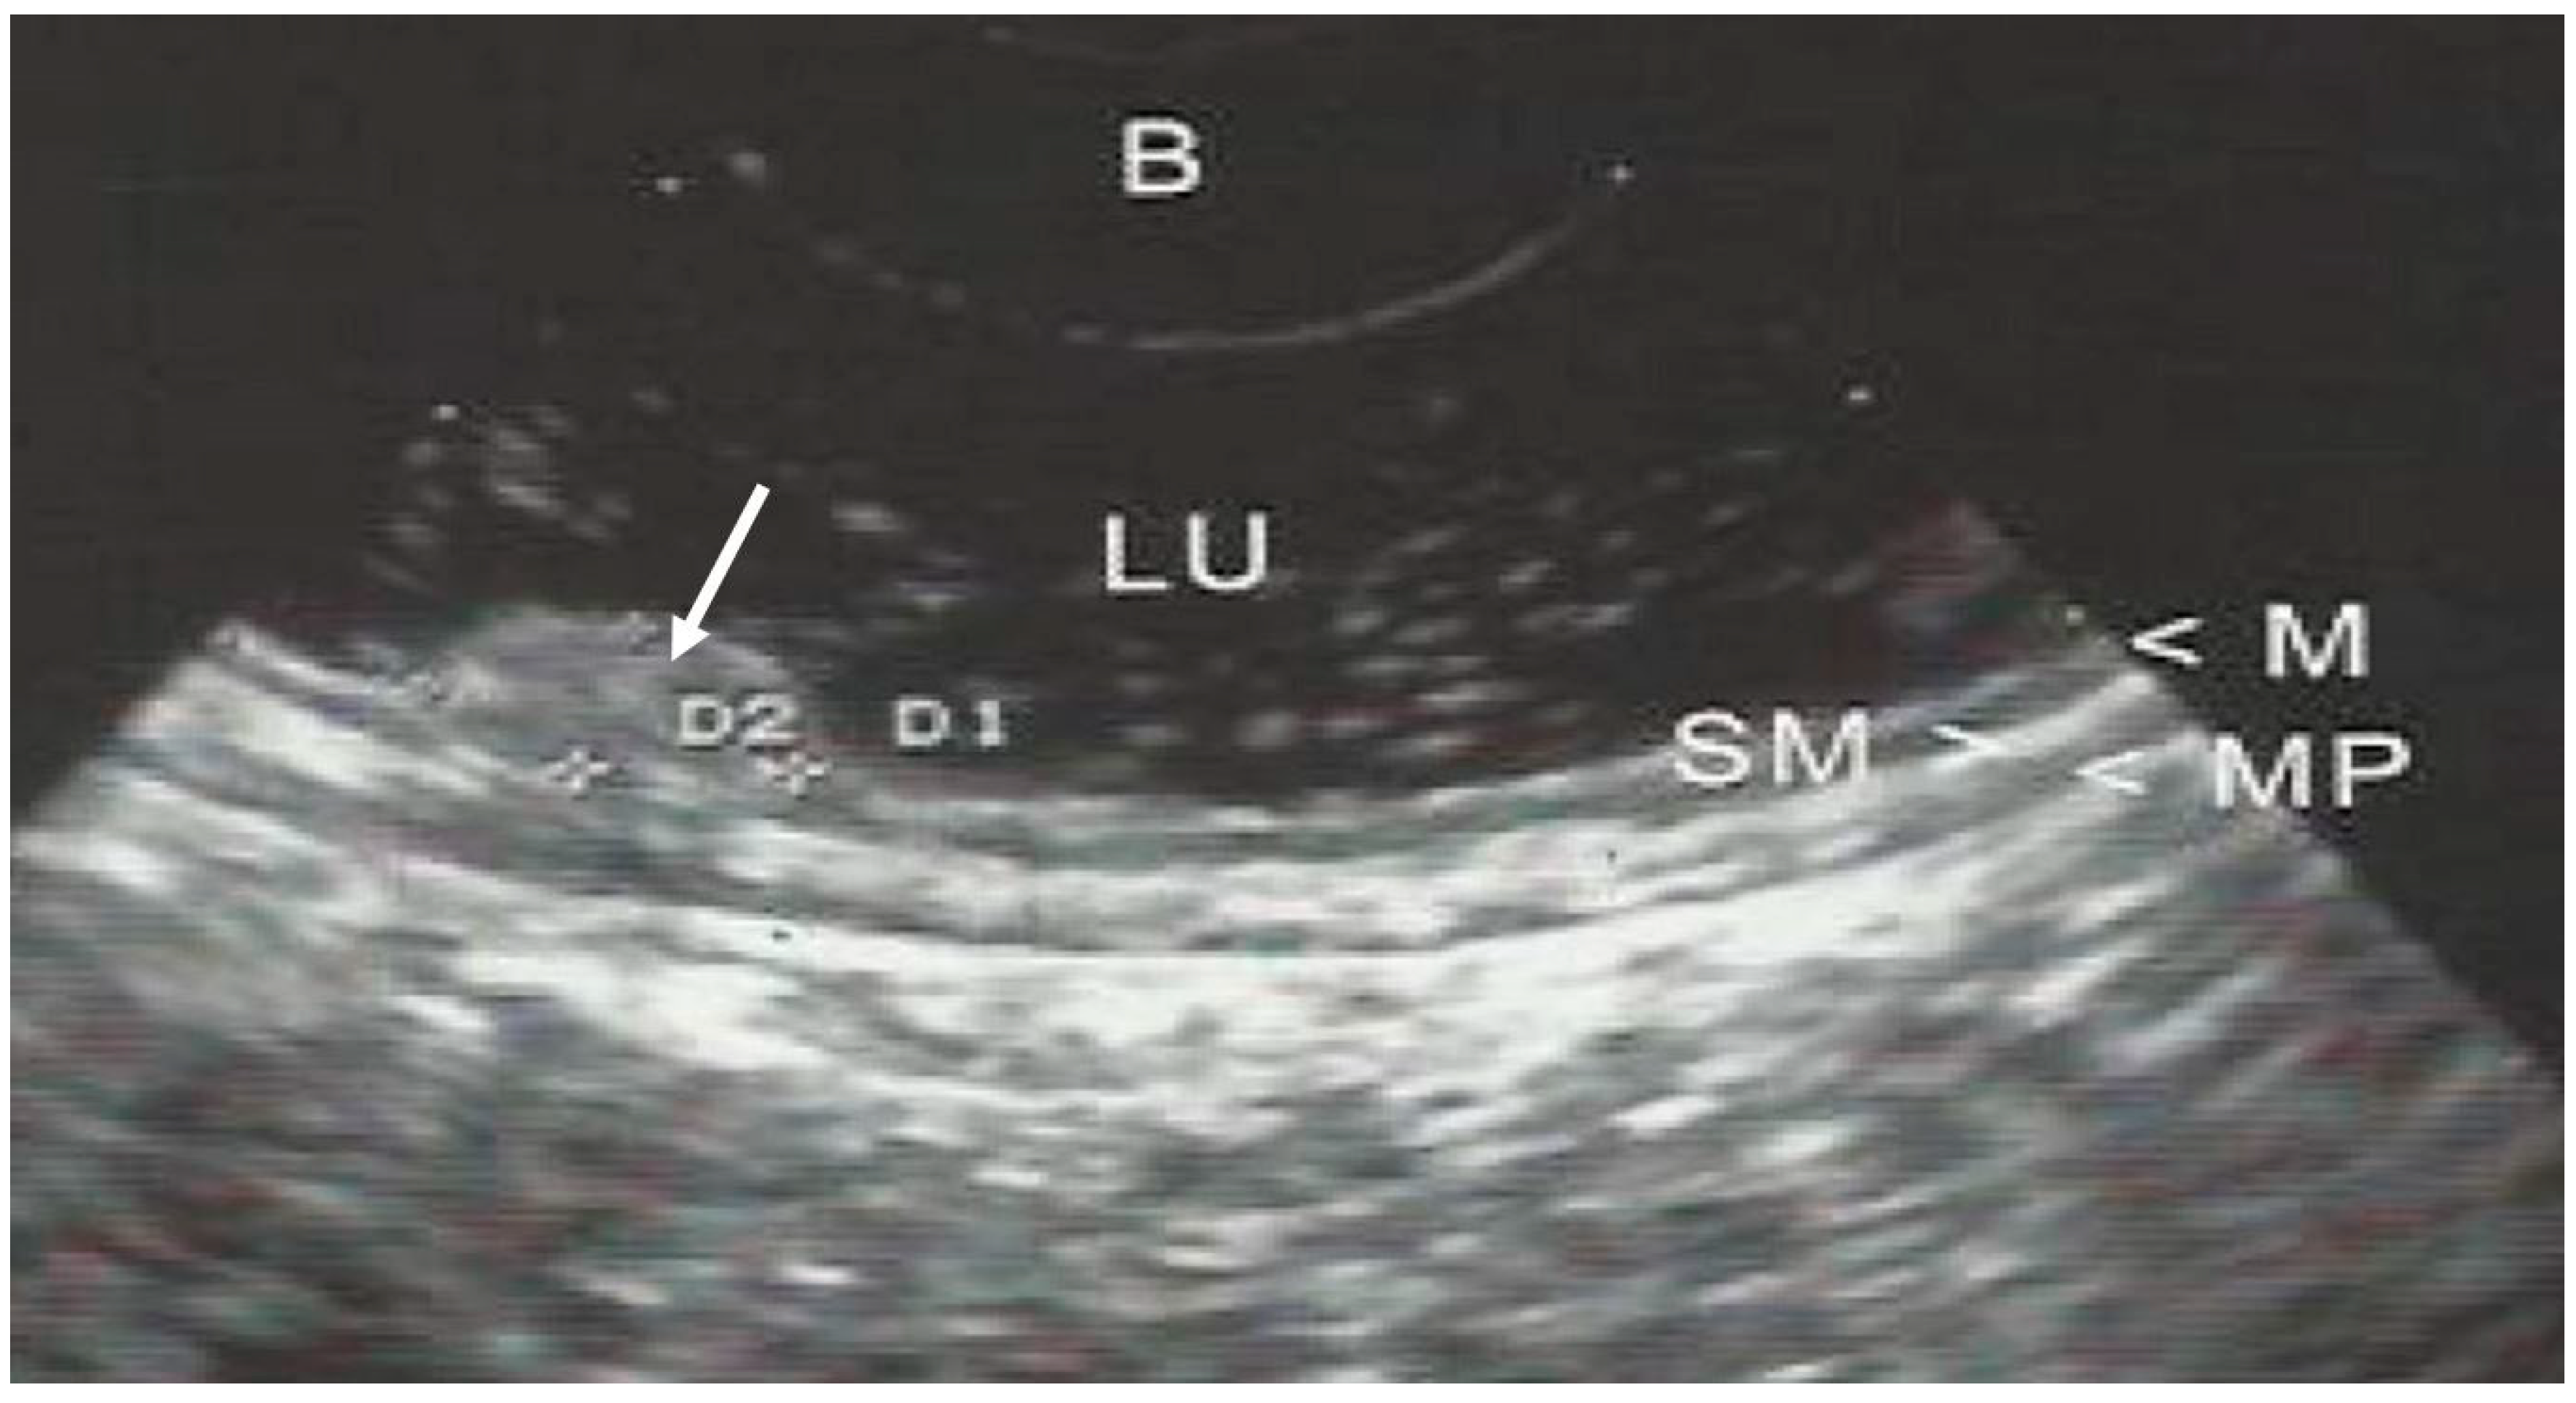

3. EUS Technique